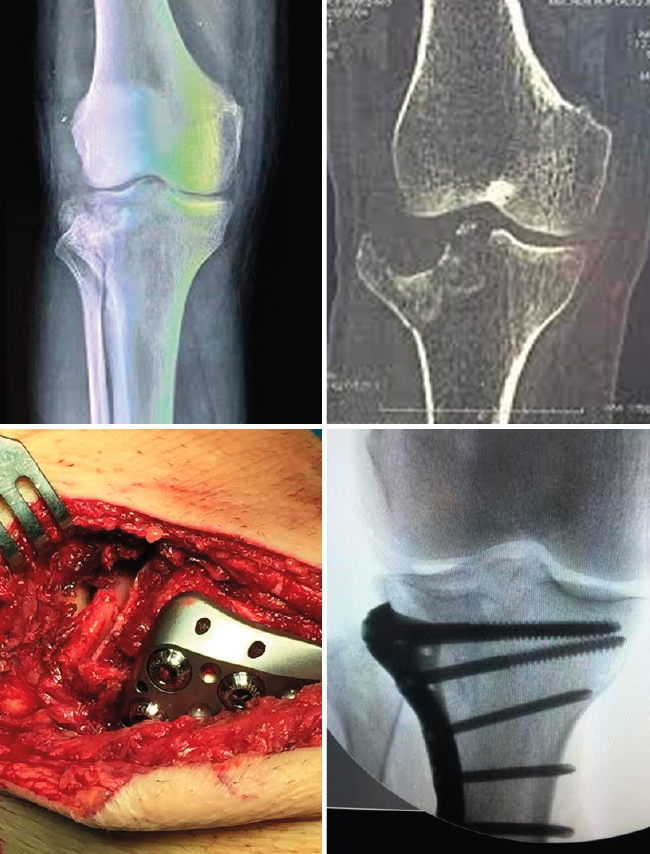

Los abordajes clásicos para el tratamiento quirúrgico de las fracturas de meseta tibial son el anterolateral, el anteromedial y el longitudinal en la línea media. Este último sería ideal en aquellas fracturas que afecten a la meseta medial y lateral en pacientes por encima de los 50-55 años, ya que posiblemente precisen la implantación de una prótesis total de rodilla por gonartrosis secundaria. La vía anterolateral es la más utilizada en virtud de la mayor frecuencia de las fracturas del platillo externo que afectan a la columna anterolateral (Figura 5). La vía anteromedial se emplea para fracturas exclusivamente del platillo interno con afectación de la columna anteromedial. Para fracturas bituberositarias anteriores, podemos emplear un doble abordaje lateral y medial, o decantarnos por una única vía longitudinal en la línea media.

Figura 5. Tratamiento de una fractura de meseta tibial mediante fijación interna y osteosíntesis.